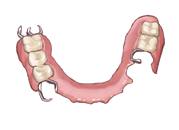

2つ目は入れ歯です

2つ目は入れ歯です 失った粘膜の部分に人口の歯がついた歯茎をつけます。

ただしそのままでは動いてしまうので前後の歯に金具をかけて動かないようにします。

取り外しをして毎日洗浄をして使っていきます。